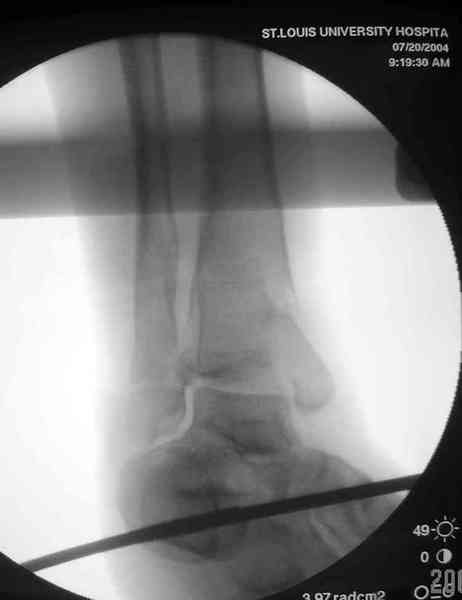

Добавлены КТ снимки. Прошу прощения за качество.

С уважением, Коваленко А.Н.